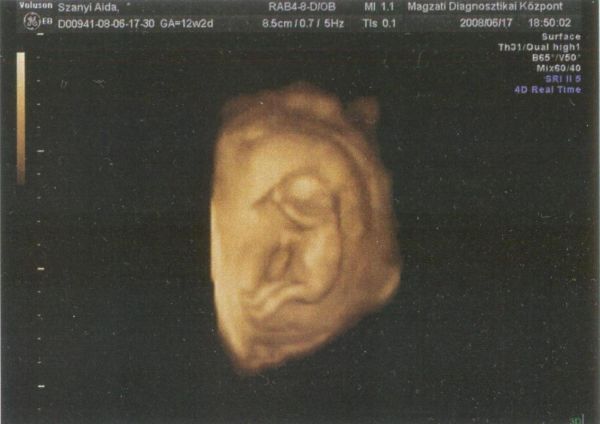

Bb-vel egyetértek, tudom, hogy mindenki szeretne már minél élesebb és minél több képet a babájáról, de én is úgy vélem, hogy a 20. hétig nagyon ritka amikor "élvezhető" az, amit látni tudok rajta. Ezt most nagyon sok idézőjelbe tenném, mert persze tudom én, hogy már magában az is élvezet, mikor látjátok a babátokat, szóval kérlek ÉRTSÉTEK JÓL, amit írok!

Mi "csak" 2d-n láttuk Angyalkánkat, és nem is minidg tudtam, hogy az most épp a feje, vagy a popsija

, de a lényeg az volt, hogy dobog a szíve, szépen mocorog és megvan mindene. Persze ha fizettek érte és azt "ígérik", hogy jól fog látszódni a baba, akkor "jogosan" lehettek felháborodva-némely esetben-, hogy nem azt kaptátok, amit vártatok, amiért fizettetek.